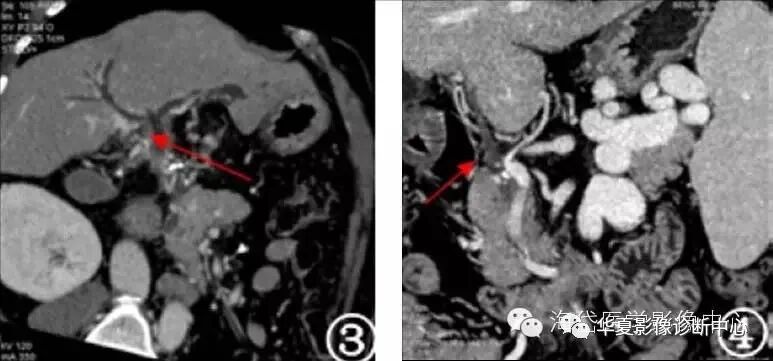

图1 门静脉主干及分支血栓伴侧枝血管建立

图2 门静脉血栓伴广泛侧枝循环建立